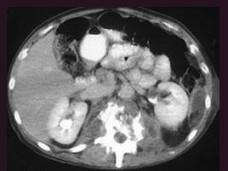

问题 男,64岁,发热,腰部疼痛半月余,请结合影像学检查,选出最可能的诊断 ( )

选项 A、脊椎骨髓瘤 B、脊椎骨髓炎 C、椎体压缩性骨折 D、脊椎转移瘤 E、脊椎结核

答案 B